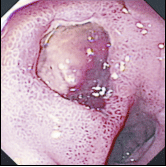

十二指腸靜脈曲張2.上消化道內鏡檢查 內鏡下十二指腸可見腸壁靜脈曲張,呈囊狀或結節狀隆起,色澤可呈藍色或與周圍黏膜一致,表面可有糜爛,覆有少許灰黃苔或血性物。與上消化道造影同樣,須與息肉和黏膜下腫瘤鑑別。活檢可能引起大出血,要特別注意,為預防活檢出血,活檢之前對隆起部分可用活檢鉗壓迫,以確定其彈性。活動出血時診斷困難,由於十二指腸有多量血液積聚,有必要反覆把血液沖洗吸引乾淨後詳細觀察黏膜面。出血者隆起病變的表面常有糜爛,並多表現為湧出性出血。即使是出血當時也難以立即作出十二指腸靜脈曲張診斷。既往史懷疑靜脈曲張破裂出血者,內鏡檢查時要想到本病並儘量插鏡到十二指腸遠端。